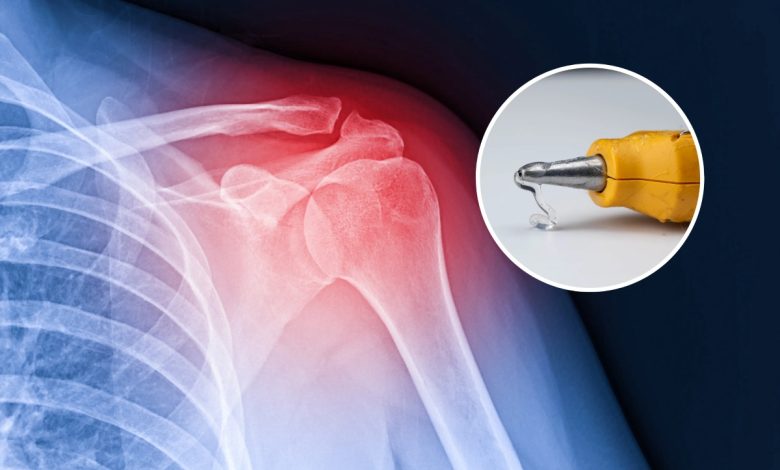

شکستگی استخوانها دردناکاند و ترمیم آنها عموماً فرآیندی زمانبر است که چند ماه طول میکشد، اما به لطف این چسب جدید استخوانی، روند درمان میتواند سریعتر شود. این محصول که «Bone-02» نامیده شده، توسط محققی در دانشگاه ژِجیانگ در هانگژو ساخته شده و تاکنون در بیش از ۱۵۰ مورد آزمایشی به کار رفته است.

در این روش، با یک تزریق ساده، قطعات استخوان شکسته شده به هم «چسبانده» میشوند؛ گفته میشود این چسب استخوانی در عرض سه دقیقه استخوان را تثبیت میکند. این توضیح را لین سیانفنگ، جراح ارتوپدی در بیمارستان Sir Run Run Shaw هانگژو، ارائه کرده است.

یکی از نمونههای منتشر شده، بیماران دارای شکستگی مچ است که طی یک برش کوچک ۳ سانتیمتری، چسب تزریق شد و ظرف سه دقیقه ترمیم اولیه صورت گرفت. اگر این ترمیم به روش جراحی معمول انجام میشد، لازم بود از پلاک فلزی و پیچ استفاده شود و در سال بعد نیز عمل دوم برای خارج کردن آن انجام شود. اما پس از پیگیری سه ماهه، بیمار بهبودی کامل و بدون عوارض داشت.